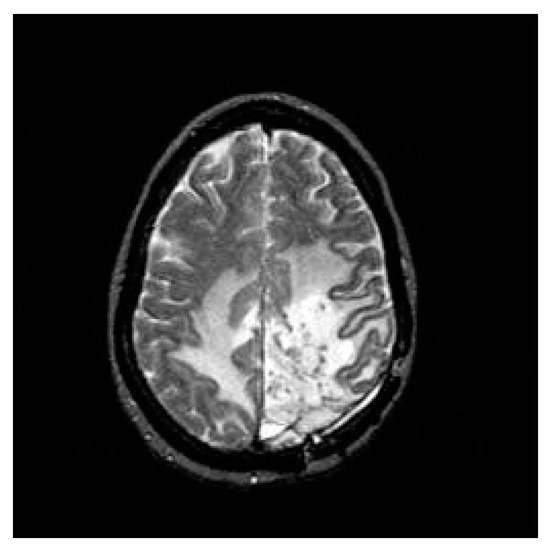

3.2. Segmentation

3.2.1. Otsu’s Threshold

3.2.2. Fuzzy C-Means Clustering (FCM)